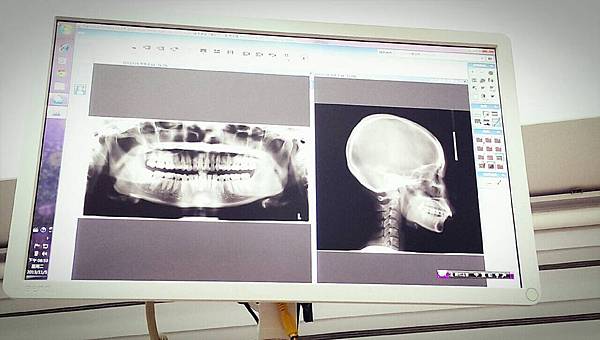

• 今日看報告嚕~我想快快上牙套~~~吶喊!!!

今天是大日子!!!OH!錯了是小日子 = 3= 只是看報告

但小女子我還是緊張又害怕

準時報到

看到和藹的醫生,拿起上次做好的牙齒模型

(繼續閱讀...)